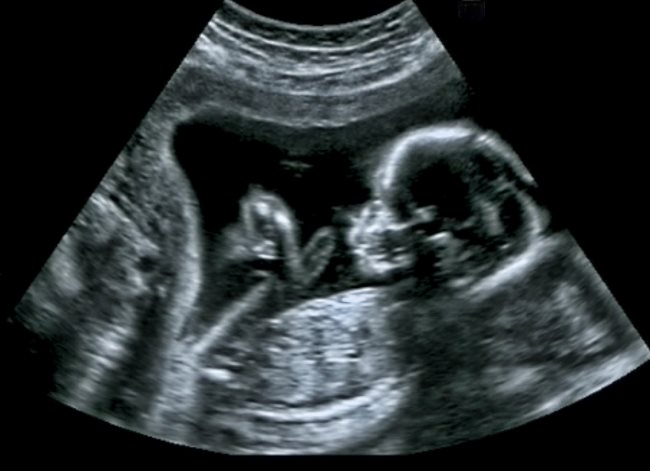

Di usia kehamilan 30 minggu, pertumbuhan janin berlangsung sangat pesat. Organ-organ penting, seperti paru-paru dan otak terus berkembang untuk mempersiapkan janin menghadapi kehidupan di luar rahim.

Selain itu, lapisan lemak di bawah kulit janin juga mulai menebal sehingga tubuh janin terlihat makin berisi. Nah, perubahan fisik ini membuat berat janin 30 minggu meningkat cukup signifikan bila dibandingkan dengan minggu-minggu sebelumnya.

Rata-rata berat janin pada usia 30 minggu umumnya berkisar antara 1,3–1,5 kg, dengan panjang dari kepala hingga tumit sekitar kurang lebih 39 cm. Ukuran ini kurang lebih setara dengan kubis berukuran besar.